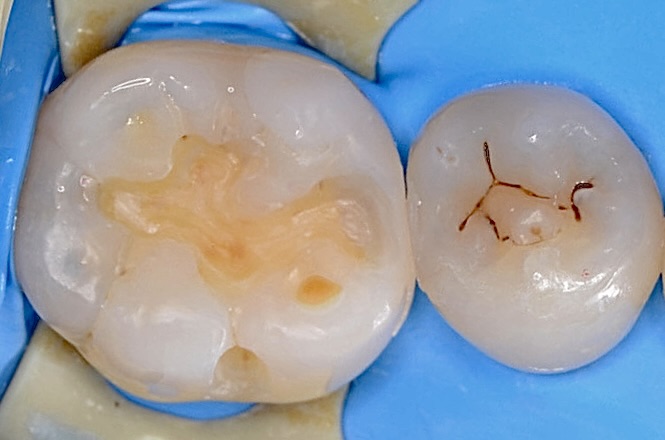

ラバーダム装着

虫歯治療においてもラバーダム装着は必須です。 唾液や血液から歯面が汚染されるのを防ぎ、乾燥状態を保つラバーダムは、接着力を向上させるためにも大切なアイテムです。 古いレジンを外したところです。それほど虫歯は深くありませんでした。 -